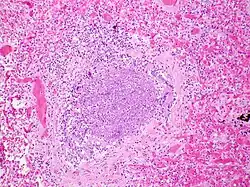

La période d'incubation est de deux à huit jours, puis le virus se multiplie dans la muqueuse nasale (une rhinopharyngite inaugure ainsi fréquemment une bronchiolite). Il gagne ensuite les voies respiratoires inférieures pour atteindre les bronchioles où il se multiplie, au sein des cellules épithéliales.

Le tableau clinique est dû à une obstruction des voies aériennes, d'une part causée par un bouchon muqueux obstruant la lumière, d'autre part due à une inflammation de la paroi bronchique. Le bouchon muqueux est créé par l'accumulation de cellules mortes et de sécrétions muqueuses. L'obstruction n'est que peu liée au spasme bronchique, les muscles lisses étant encore peu développés à cet âge.